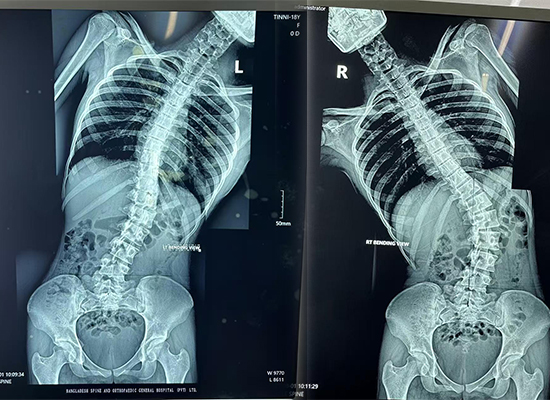

L'imagerie préopératoire a montré :

Courbure latérale marquée du rachis thoraco-lombaire

Rotation vertébrale et proéminence des côtes

Déséquilibre des épaules et alignement du tronc

Ces résultats ont confirmé la nécessité d' une correction et d'une fusion de la déformation rachidienne postérieure à l'aide d'une construction vis-tige pédiculaire..

Radiographie préopératoire de toute la colonne vertébrale montrant une scoliose thoraco-lombaire chez un patient de 16 ans de Dhaka, Bangladesh.